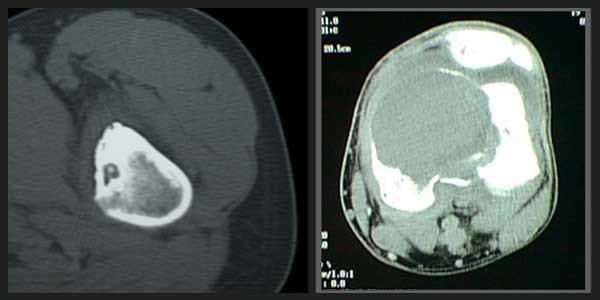

Liposarkom

Kötü huylu yumuşak doku tümörleri arasında ikinci sıklıktadır. Nedeni tam olarak bilinmemektedir. Çok farklı yaşlarda görülebilir fakat sıklıkla 40 yaş sonrası ortaya çıkar.